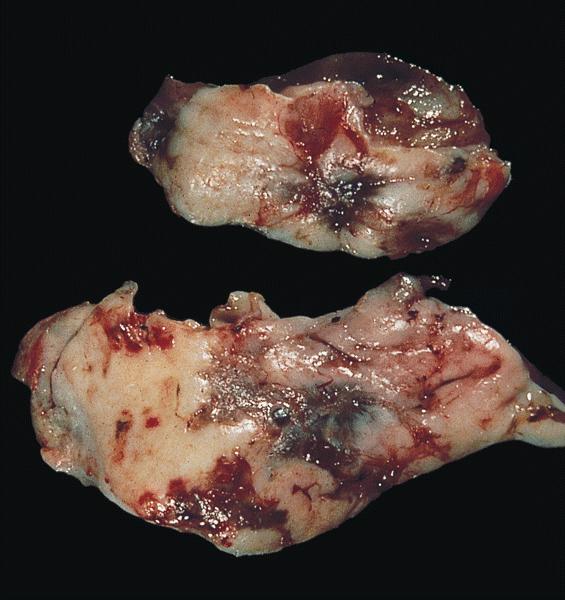

Gross description

- Ovarian endometriotic cysts (endometriomas) have fibrotic walls, a smooth lining and dark brown cyst contents (chocolate cyst), often adherent to adjacent organs

- Polypoid endometriosis has a polypoid configuration that raises the differential diagnosis of a neoplasm on gross and intraoperative examination (Am J Surg Pathol 2004;28:285)

- Red, brown, white plaques, sometimes with a gelatinous appearance (Arch Gynecol Obstet 2015;292:1295, Taiwan J Obstet Gynecol 2019;58:328)

Gross images